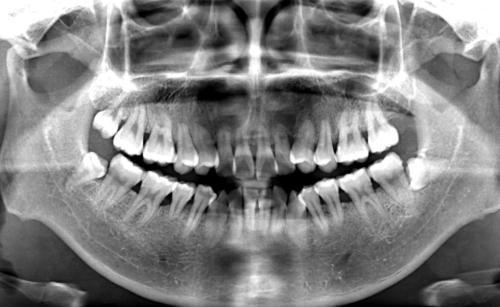

发现问题后,我没有轻易放弃,我再次找到了主诊医生,详细描述了我的症状和疑虑,医生也承认了部分问题的存在,并安排了进一步的检查(如X光片、牙龈探诊等),经过仔细检查,医生确认了我的牙龈存在炎症迹象,边缘也存在微小的不密合,他解释了可能的原因,并制定了一个治疗计划:进行专业的牙周洁治和种植体周围维护,对修复体进行微调,甚至建议进行牙龈组织的增厚(牙龈增生或引导性组织再生)以改善美观和健康状况。